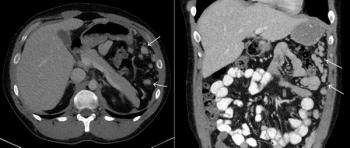

A 56-year-old woman presents with abdominal fullness and virilization. Axial and coronal images from a CT scan of her abdomen are shown below. What is your diagnosis?